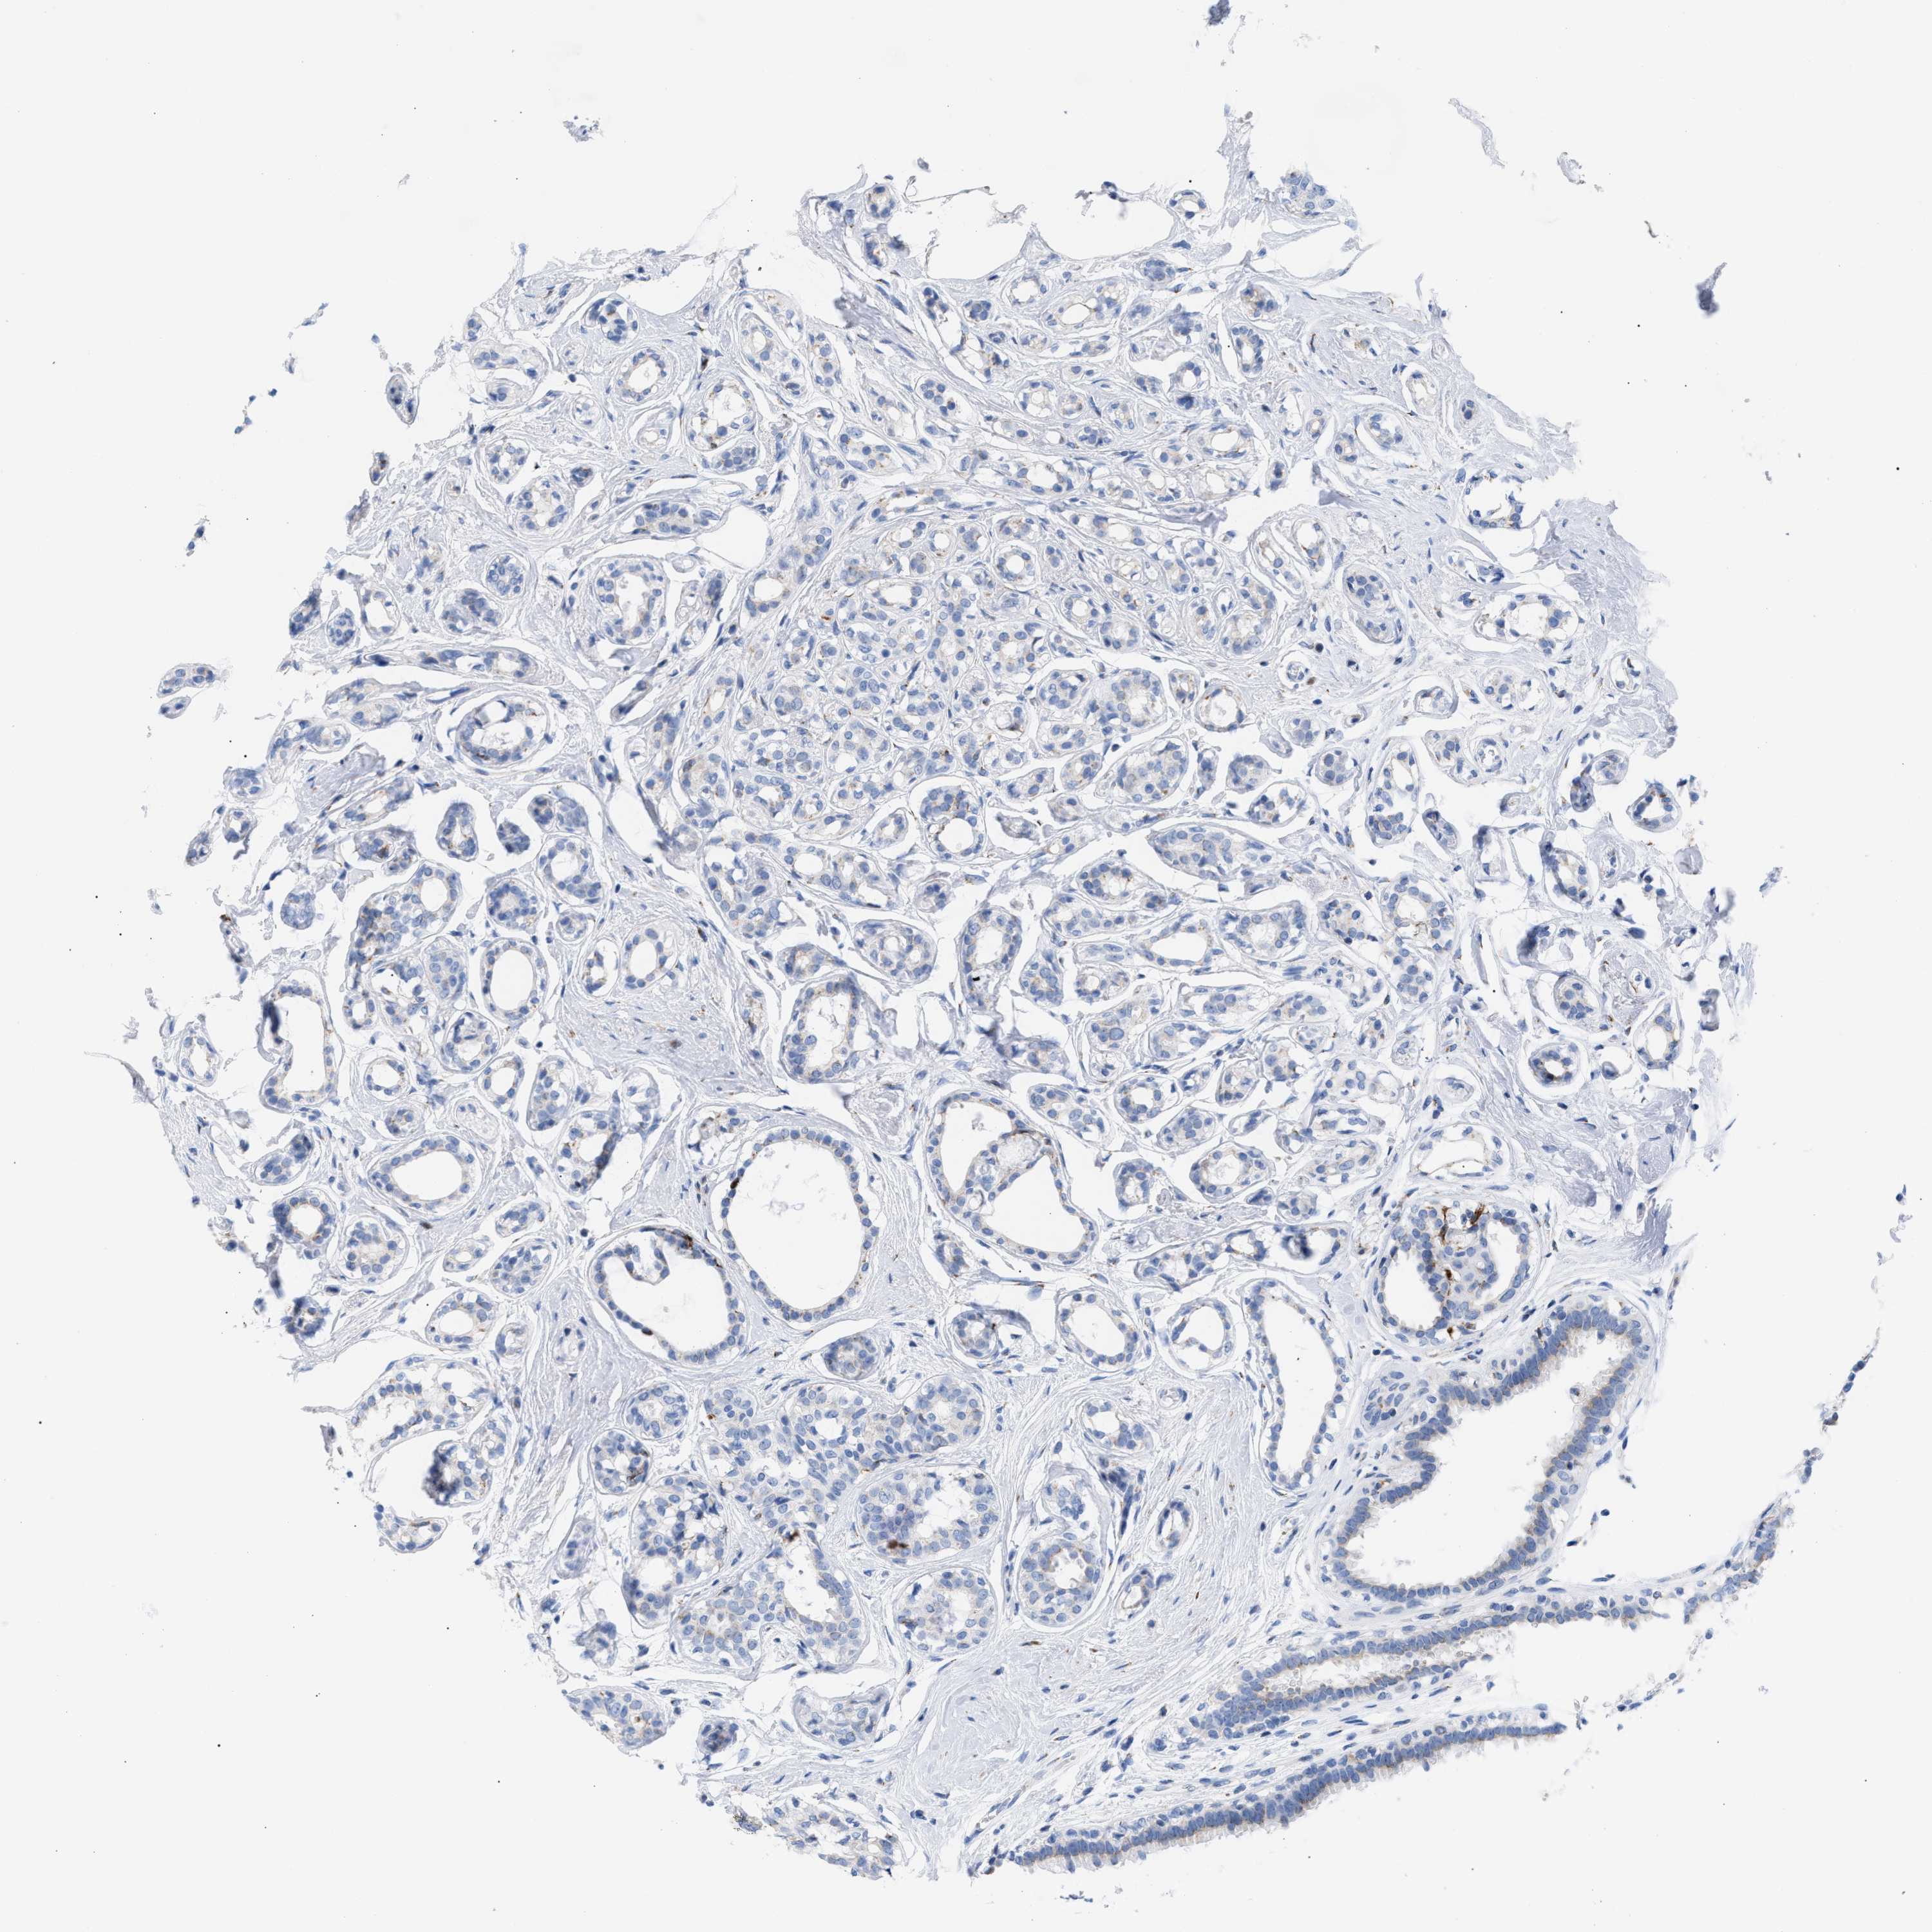

CANCER BREAST CANCER Show tissue menu

BRCA TCGA BRCA VALIDATION PROTEIN EXPRESSION